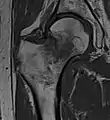

Typically, radiographs are taken of the hip from the front (AP view), and side (lateral view). Frog leg views are to be avoided, as they may cause severe pain and further displace the fracture.[5] In situations where a hip fracture is suspected but not obvious on x-ray, an MRI is the next test of choice. If an MRI is not available or the patient can not be placed into the scanner a CT may be used as a substitute. MRI sensitivity for radiographically occult fracture is greater than CT. Bone scan is another useful alternative however substantial drawbacks include decreased sensitivity, early false negative results and decreased conspicuity of findings due to age-related metabolic changes in the elderly.[16]

A case demonstrating a possible order of imaging in initially subtle findings:

X-ray showing a suspected compressive subcapital fracture as a radiodense line

CT scan shows the same, atypical for a fracture since the cortex is coherent

T1-weighted, turbo spin echo, MRI confirms a fracture, as the surrounding bone marrow has low signal from edema.